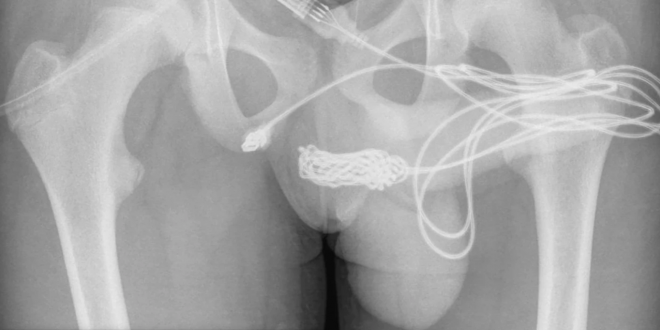

When he tried to remove it, the cord got tangled, and both USB ends were hanging out of his privates. He was immediately taken to the hospital; he was urinating blood. The first attempts to remove the wires didn’t work, so he had to be transferred to University College Hospital London.

Doctors had to make an incision near his genitals and anus to get the cord out. The boy recovered from the procedure and was able to be discharged from the hospital the next day. But, he will have to be scanned in a follow-up appointment, and he will be monitored for some time.